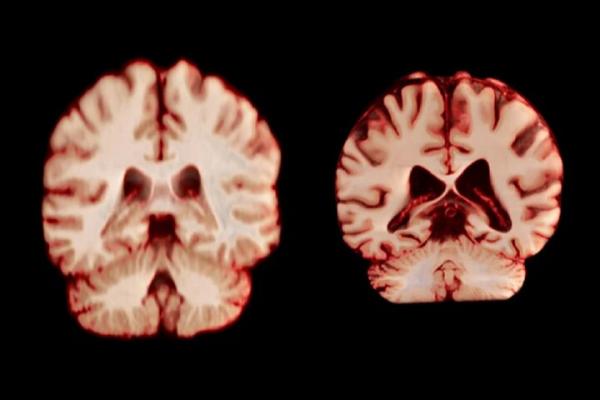

اسکن مغز

جدیدترین مطالعه شامل بیش از ۱۲ هزار و ۵۰۰ اسکن مغزی تصویربرداری تشدید مغناطیسی (MRI) از ۴۷۲۶ نفر بود که حداقل دو اسکن برای هر نفر، با فاصله متوسط سه سال انجام شده بود که به بیماری آلزایمر یا هرگونه اختلال شناختی مبتلا نبودند و به عنوان شرکتکننده کنترل در ۱۴ مجموعه داده بزرگتر قرار داشتند. محققان با بررسی عواملی از جمله ضخامت ماده خاکستری و اندازه نواحی مرتبط با بیماری آلزایمر، مانند هیپوکامپ که برای حافظه ضروری است، نحوه تغییر ساختار مغز افراد را در طول زمان مقایسه کردند.

به طور کلی، مردان در مقایسه با زنان، کاهش حجم بیشتری را در مناطق بیشتری از مغز تجربه کردند. به عنوان مثال، قشر پس مرکزی که مسئول پردازش احساسات لامسه، درد و دما و همچنین موقعیت و حرکات بدن است، در مردان سالانه ۲.۰ درصد و در زنان سالانه ۱.۲ درصد کاهش یافت.